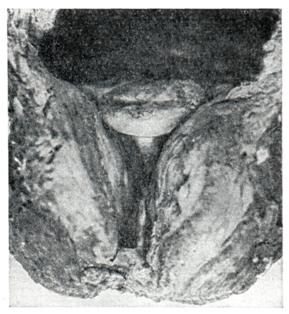

Эндоскопические методы исследования — цистоскопию, уретроскопию (см.) — следует проводить только при гематурии, подозрении на опухоль мочевого пузыря или для дифференциальной диагностики в неясных случаях. Уретроскопия показана в ранней стадии заболевания и не у пожилых, больных. При цистоскопии выявляются выбухания переходной складки в виде занавески (рис. 9), определяется средняя доля в виде барьера, уточняется наличие камней и сопутствующих заболеваний — цистита, язвы, папилломы. Во II и III стадиях заболевания цистоскопия затруднительна, может быть причиной развития инфекции, возникновения простатита и эпидидимита. Поэтому в последние годы большинство урологов предпочитает проводить цистоскопию в операционной перед операцией.

Рис. 9. | ||